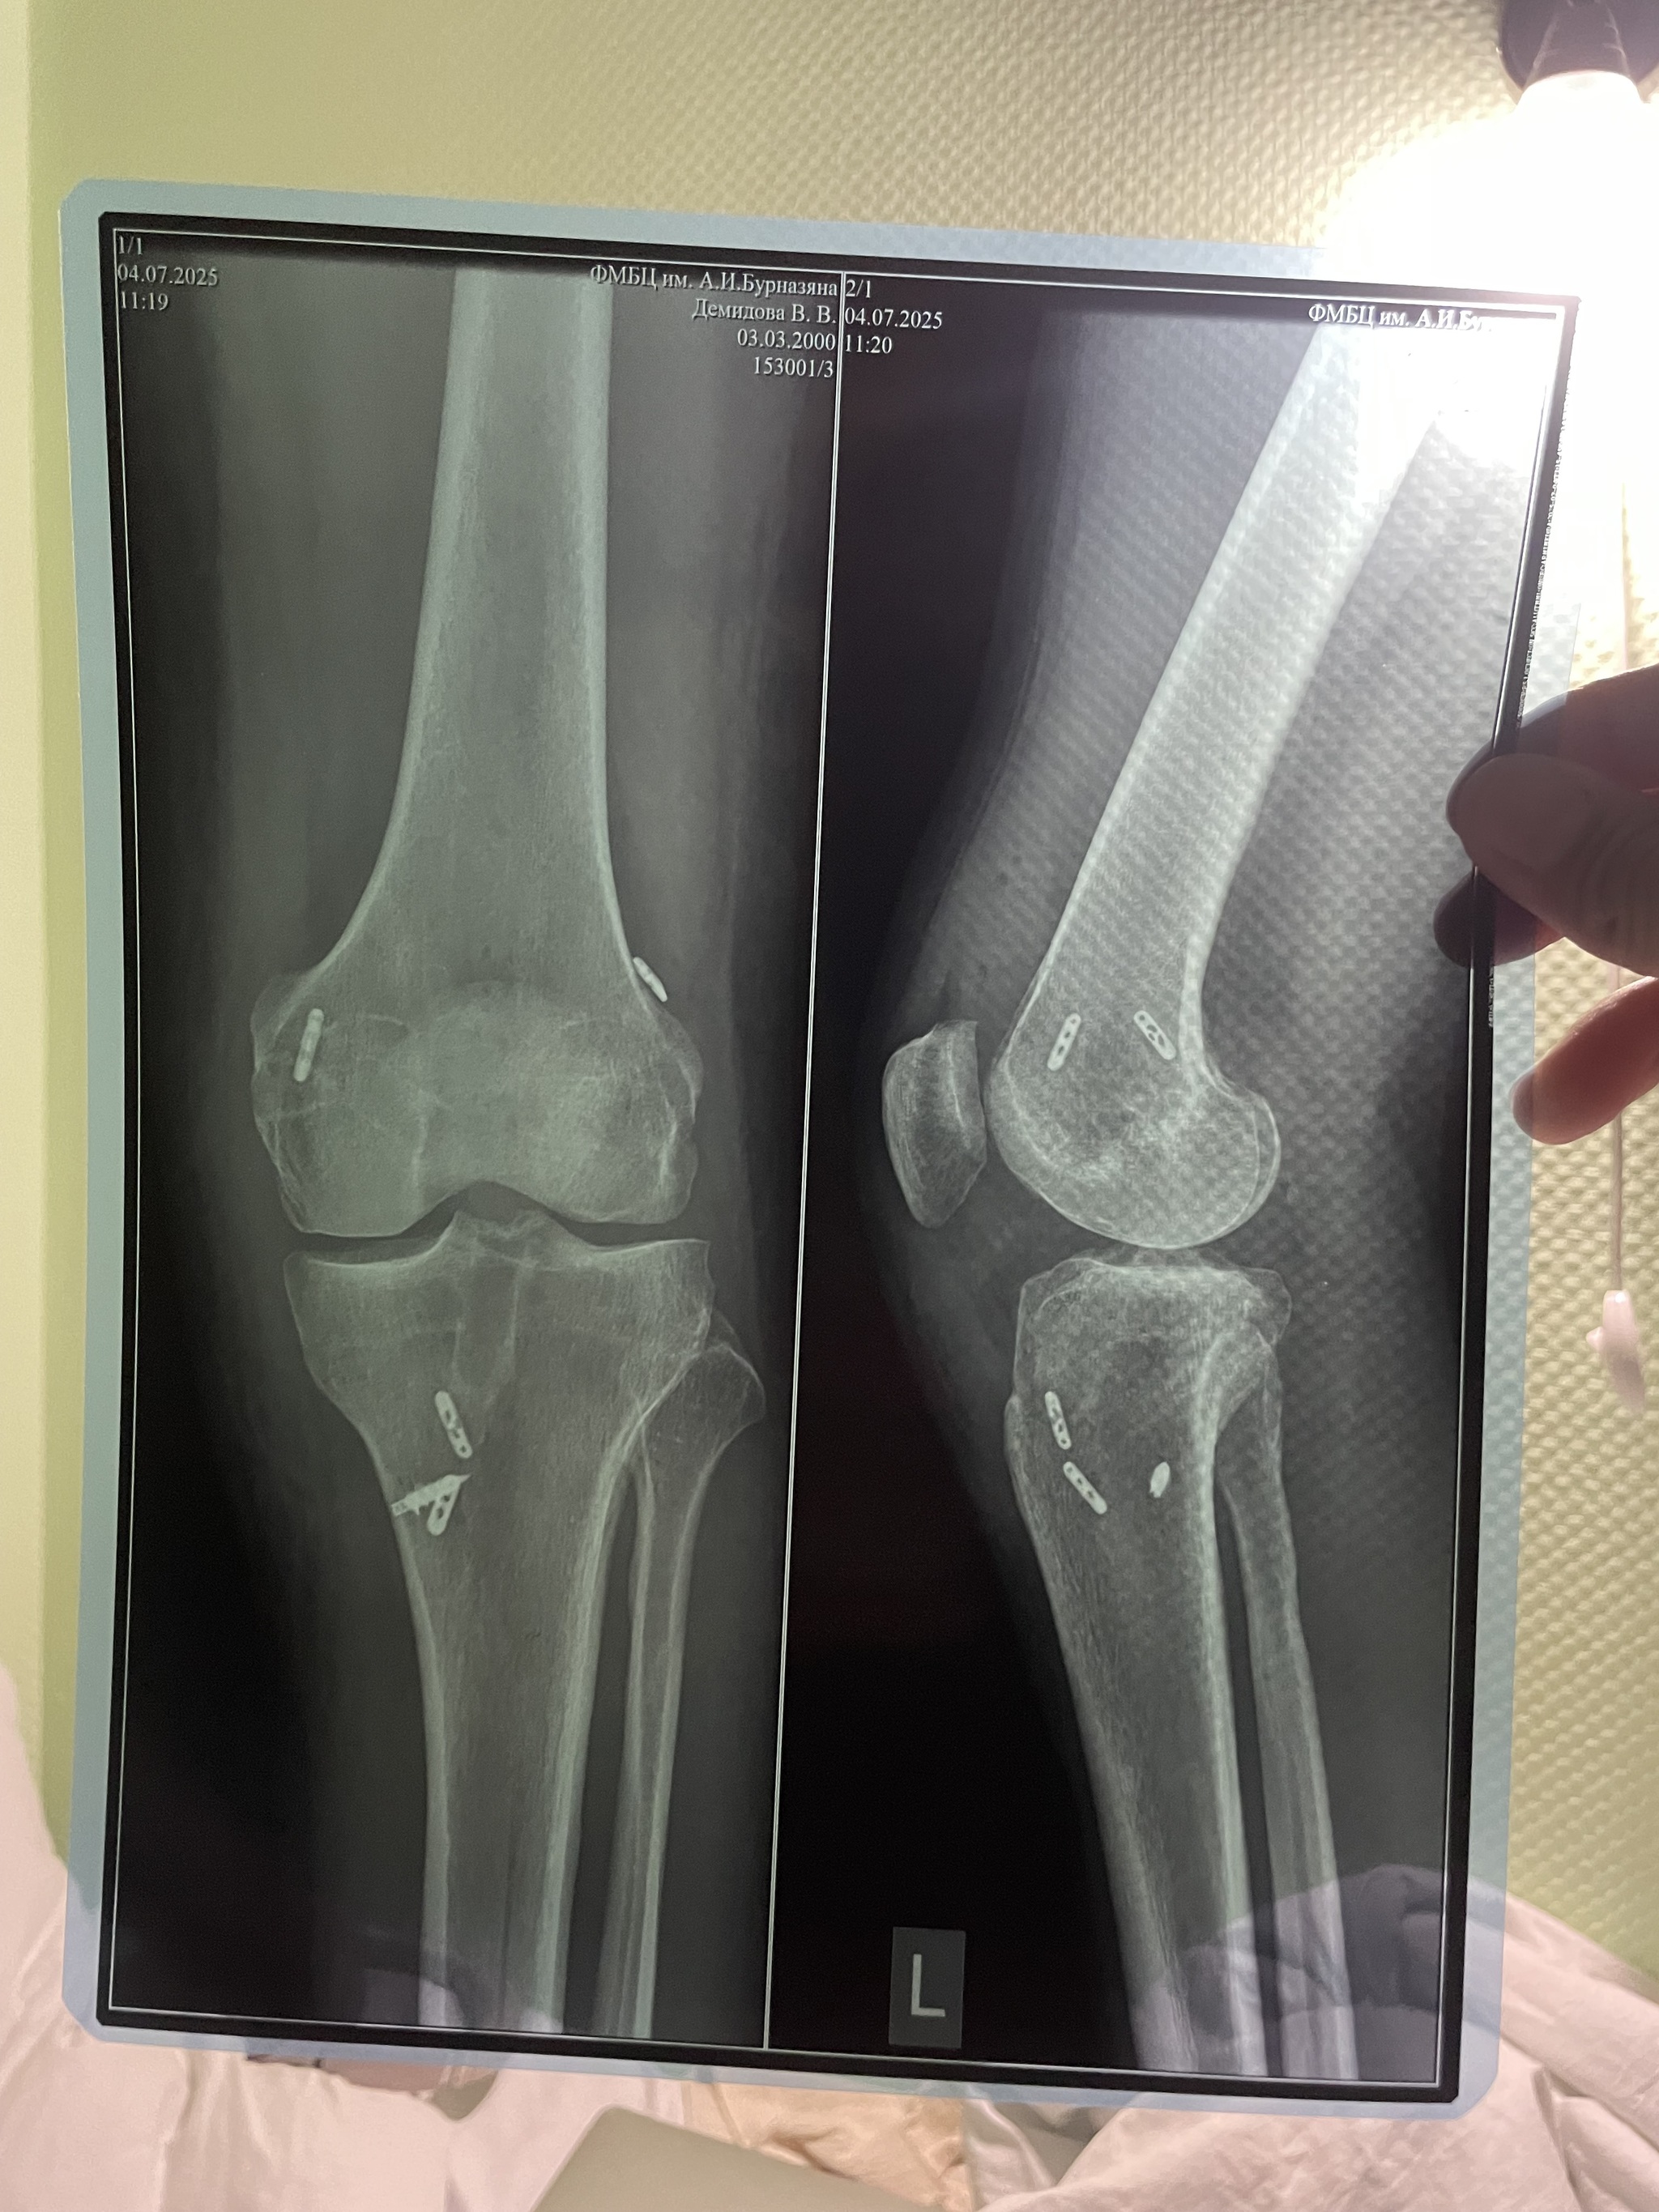

Пришло время второй операции на колено, где мне трансплантировать сухожилие из голеностопа в колено и создали новую переднюю крестообразную связку.

Не могу сказать, что реабилитация и восстановление дается просто, но с улыбкой на лице, конечно, проще проходить через трудности. Реабилитация, сгиб-разгиб, отеки, синяки — стандартная процедура. На сегодняшний день прошло 5 месяцев, самое неприятное, что колено затекает. Что это значит? Посидел 2 часа - встать не можешь. Сначала надо медленно разогнуть колено и потом его «расходить», но, говорят, со временем эта проблема уходит.

Через 3 месяца после операции делала МРТ. Итог: присутствует небольшое разволокнение и отек. С отеком ладно, более менее норма, а со связкой придется потерпеть еще немного. Жду МРТ в конце месяца и будет понятно что делать дальше. Можно ли давать нагрузки на ногу или же ложиться на операционный стол для чистки переднего креста.